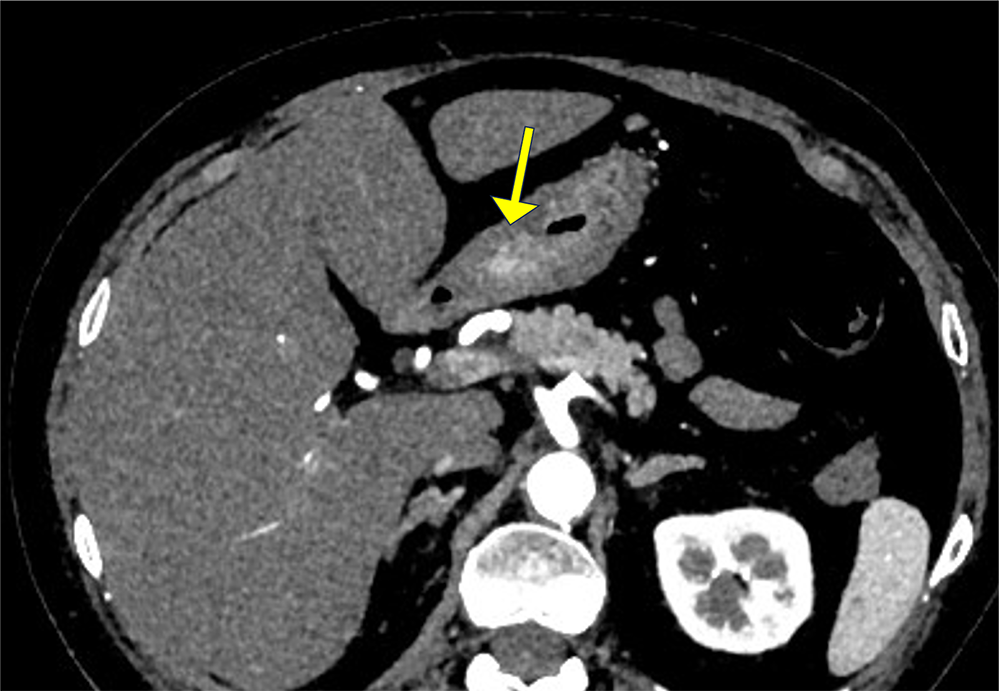

胃体下部小弯側に早期動脈相で他の粘膜面と比較して造影効果の強い領域が認められる。指摘されている胃癌病変を見ているものと考えられる。

胃周囲にはリンパ節と考えられる13mm程度の結節病変を複数個認め、リンパ節転移が疑われる。腹部傍大動脈域に病的有意なリンパ節腫大は認められない。本症例は、腹腔鏡下幽門側胃切除術が施行され、進行胃癌および領域リンパ節転移と診断された。

門脈相ではDualEnergyを用いており、血管走行(門脈)の造影効果が低い場合は、仮想単色X線画像にて低keV画像を作成できるように備えている。また単純もDualEnergyで撮影することで、同一の120kVp相当の画像を再構成することで臓器や病変の造影効果を確認できるようにしている。

胃癌に対する根治切除のアプローチ法はこの数年で大きく変わり、早期胃癌を中心に内視鏡治療や腹腔鏡下胃切除、ロボット支援手術が普及しつつある。これらの手術は拡大された術野での出血の少ない精緻なリンパ節廓清が特徴であるが、俯瞰した術野での病変進展範囲の把握が困難になるという課題もある。そのため、術前に十分なシミュレーションを行うために造影CTによる3D画像は有用である。正確な3D画像を作成することで外科医は血管走行を事前に把握でき、出血の回避や多臓器損傷のリスクを減少させることが可能になる。

3D画像は、息止めによる早期動脈相と門脈相の位置ずれがあった場合は、非剛体補正による位置合わせを行う。動脈は腹腔動脈からの左胃動脈、右胃動脈の起始部や大網動脈の走行、門脈では左胃静脈の流入位置を描出することが求められる。また、膵臓や脾臓の実質臓器も3D画像に含めることで、手術時の視野をイメージできるよう配慮している。